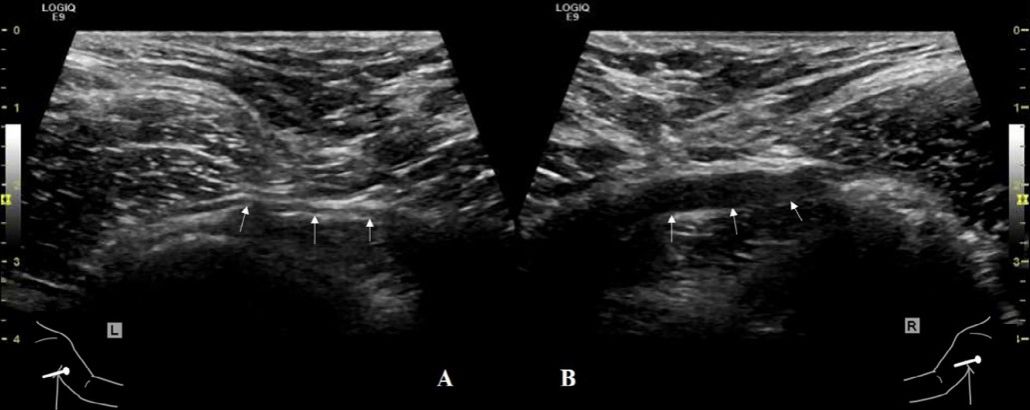

病例1:患者34岁男性,右肩受伤,活动范围受限,持续2个月。A,左侧腋神经(箭头)正常。B,与正常侧相比,右侧腋神经(箭头)回声减低,弥漫性肿胀。

病例2:51岁女性在修复肩袖撕裂后出现右肩活动范围受限,持续2个月。A,左侧三角肌(D)正常。B,右侧三角肌(D)萎缩,回声增强。C,右侧腋神经(箭头)回声减低,弥漫性肿胀。D,彩色多普勒超声显示伴随的旋肱后动脉(A)和静脉(V)。